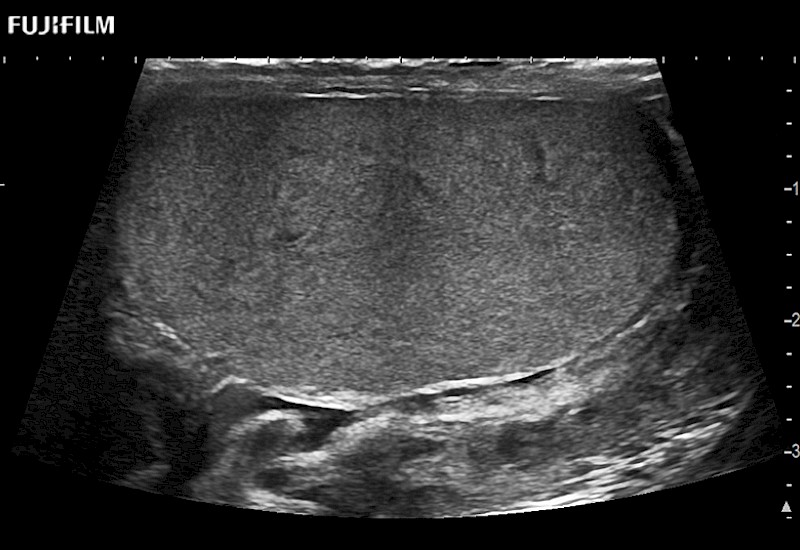

Abdominal transducer for biopsy, bladder and renal applications.